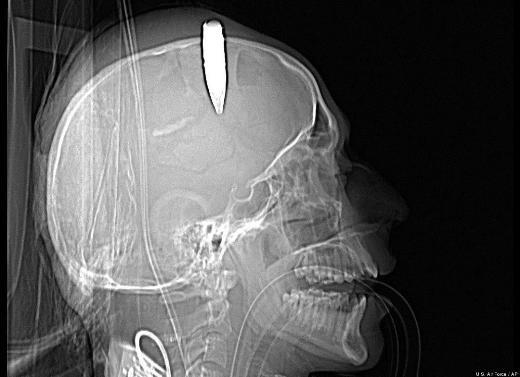

6. Bir Afgan askerine ait CT scan görüntüsünde kafatasına saplanmış 14,5 milimetrelik patlamamış kurşun görülüyor. ABD'li bir askeri doktorun, kurşunu çıkardığı biliniyor.

Bir Afgan askerine ait CT scan görüntüsünde kafatasına saplanmış 14,5 milimetrelik patlamamış kurşun görülüyor. ABD'li bir askeri doktorun, kurşunu çıkardığı biliniyor.